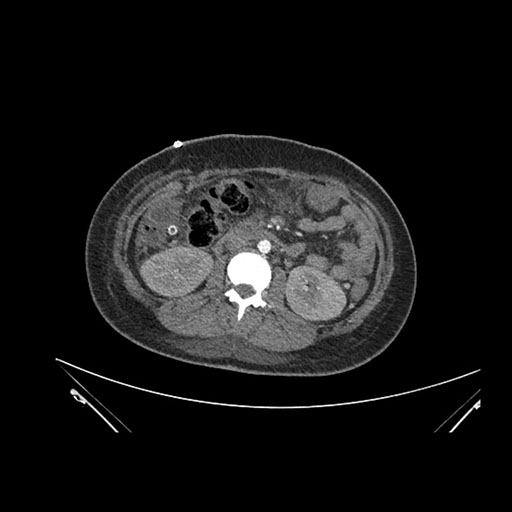

Imaging Analysis

Look through the patient's CT scan to identify any areas of concern for the necessary procedure.

Coronal Arterial